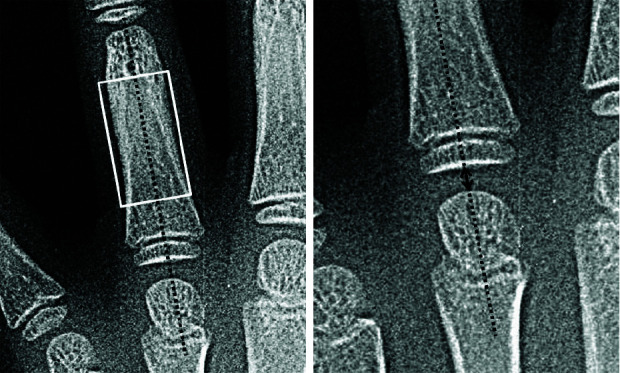

Statement of the problem: Bone age is a more accurate assessment for biologic development than chronological age. The most common method for bone age estimation is using Pyle and Greulich Atlas. Today, computer-based techniques are becoming more favorable among investigators. However, the morphological features in Greulich and Pyle method are difficult to be converted into quantitative measures. During recent years, metacarpal bones and metacarpophalangeal joints dimensions were shown to be highly correlated with skeletal age.

Purpose: In this study, we have evaluated the accuracy and reliability of a trained neural network for bone age estimation with quantitative and recently introduced related data, including chronological age, height, trunk height, weight, metacarpal bones, and metacarpophalangeal joints dimensions.